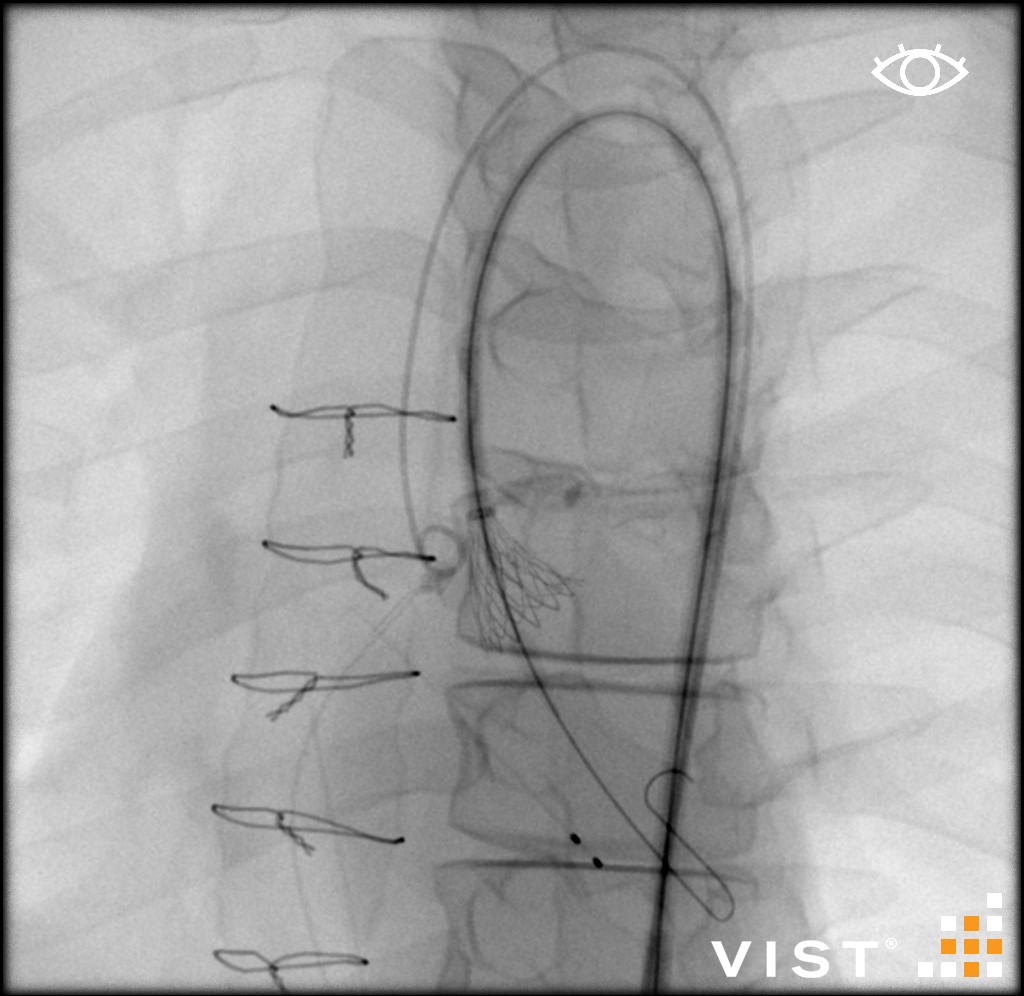

Simuladores Endovanculares.

Aquíhayuna listademódulosundonibles concatibles con el simulador vist g5(Versiónforporidenteyy lab,没有兼容的孔血管y vist灯)。Esta listaestántancoreeevolución,没有Dude en advertarla promicy ... los dutallesestándisponibles haciendo clic en eltítulodelmódulo(网站蒙黛尔,enInglés)